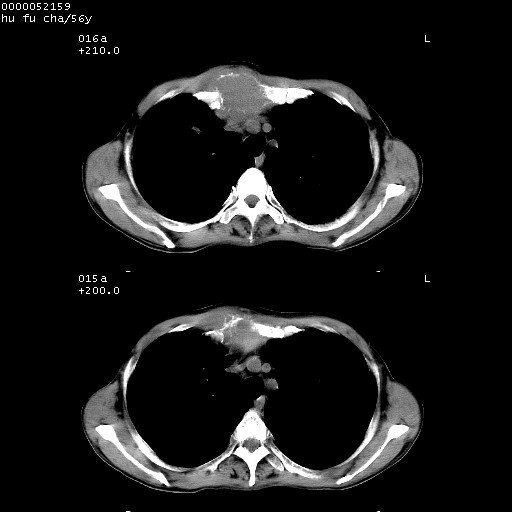

以下是引用zsl6918在2008-8-25 22:47:00的发言:[br]胸骨,胸椎及肋骨均可见多发转移表现,肝内低密度结节不除外转移。原发灶可能在右肺。双侧可见支扩表现。